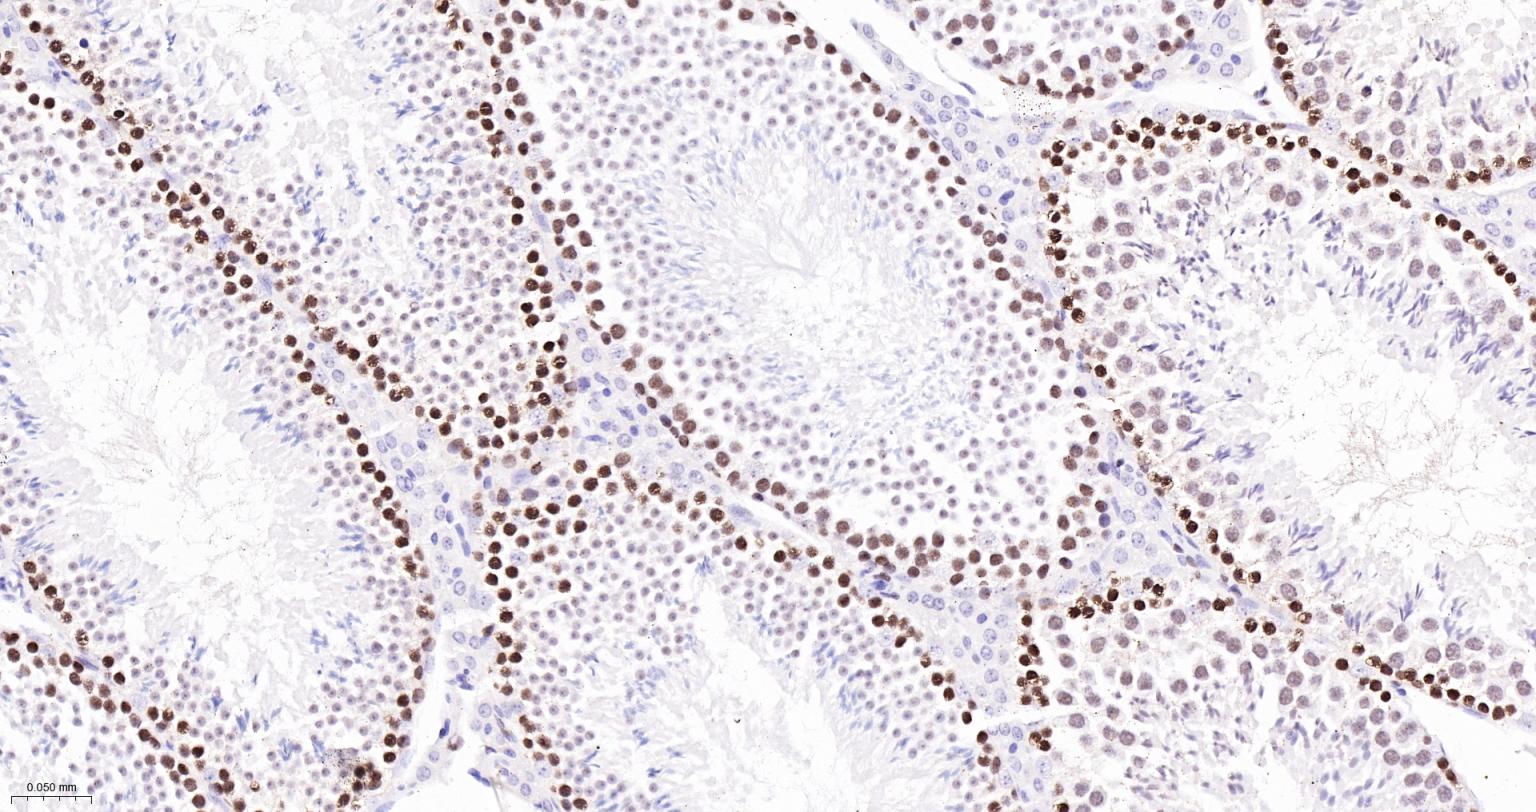

Paraformaldehyde-fixed, paraffin embedded Human Tonsil; Antigen retrieval by boiling in sodium citrate buffer (pH6.0) for 15 min; Antibody incubation with MCM2 Monoclonal Antibody, Unconjugated(bsm-63311R) at 1:200 overnight at 4°C, followed by conjugation to the bs-0295G-HRP and DAB (C-0010) staining.

Paraformaldehyde-fixed, paraffin embedded Human Breast Cancer; Antigen retrieval by boiling in sodium citrate buffer (pH6.0) for 15 min; Antibody incubation with MCM2 Monoclonal Antibody, Unconjugated(bsm-63311R) at 1:200 overnight at 4°C, followed by conjugation to the bs-0295G-HRP and DAB (C-0010) staining.

Paraformaldehyde-fixed, paraffin embedded Human Colon Cancer; Antigen retrieval by boiling in sodium citrate buffer (pH6.0) for 15 min; Antibody incubation with MCM2 Monoclonal Antibody, Unconjugated(bsm-63311R) at 1:200 overnight at 4°C, followed by conjugation to the bs-0295G-HRP and DAB (C-0010) staining.

Paraformaldehyde-fixed, paraffin embedded Human Cervical Cancer; Antigen retrieval by boiling in sodium citrate buffer (pH6.0) for 15 min; Antibody incubation with MCM2 Monoclonal Antibody, Unconjugated(bsm-63311R) at 1:200 overnight at 4°C, followed by conjugation to the bs-0295G-HRP and DAB (C-0010) staining.

Paraformaldehyde-fixed, paraffin embedded Human Lung Cancer; Antigen retrieval by boiling in sodium citrate buffer (pH6.0) for 15 min; Antibody incubation with MCM2 Monoclonal Antibody, Unconjugated(bsm-63311R) at 1:200 overnight at 4°C, followed by conjugation to the bs-0295G-HRP and DAB (C-0010) staining.

Paraformaldehyde-fixed, paraffin embedded Human Small Intestine; Antigen retrieval by boiling in sodium citrate buffer (pH6.0) for 15 min; Antibody incubation with MCM2 Monoclonal Antibody, Unconjugated(bsm-63311R) at 1:200 overnight at 4°C, followed by conjugation to the bs-0295G-HRP and DAB (C-0010) staining.

Paraformaldehyde-fixed, paraffin embedded Mouse Testicles; Antigen retrieval by boiling in sodium citrate buffer (pH6.0) for 15 min; The section was incubated with MCM2 Monoclonal Antibody, Unconjugated (bsm-63311R) at 1:200 overnight at 4°C, followed by conjugation to the bs-0295G-HRP and DAB (C-0010) staining.

Paraformaldehyde-fixed, paraffin embedded Rat Testicles; Antigen retrieval by boiling in sodium citrate buffer (pH6.0) for 15 min; The section was incubated with MCM2 Monoclonal Antibody, Unconjugated (bsm-63311R) at 1:200 overnight at 4°C, followed by conjugation to the bs-0295G-HRP and DAB (C-0010) staining.